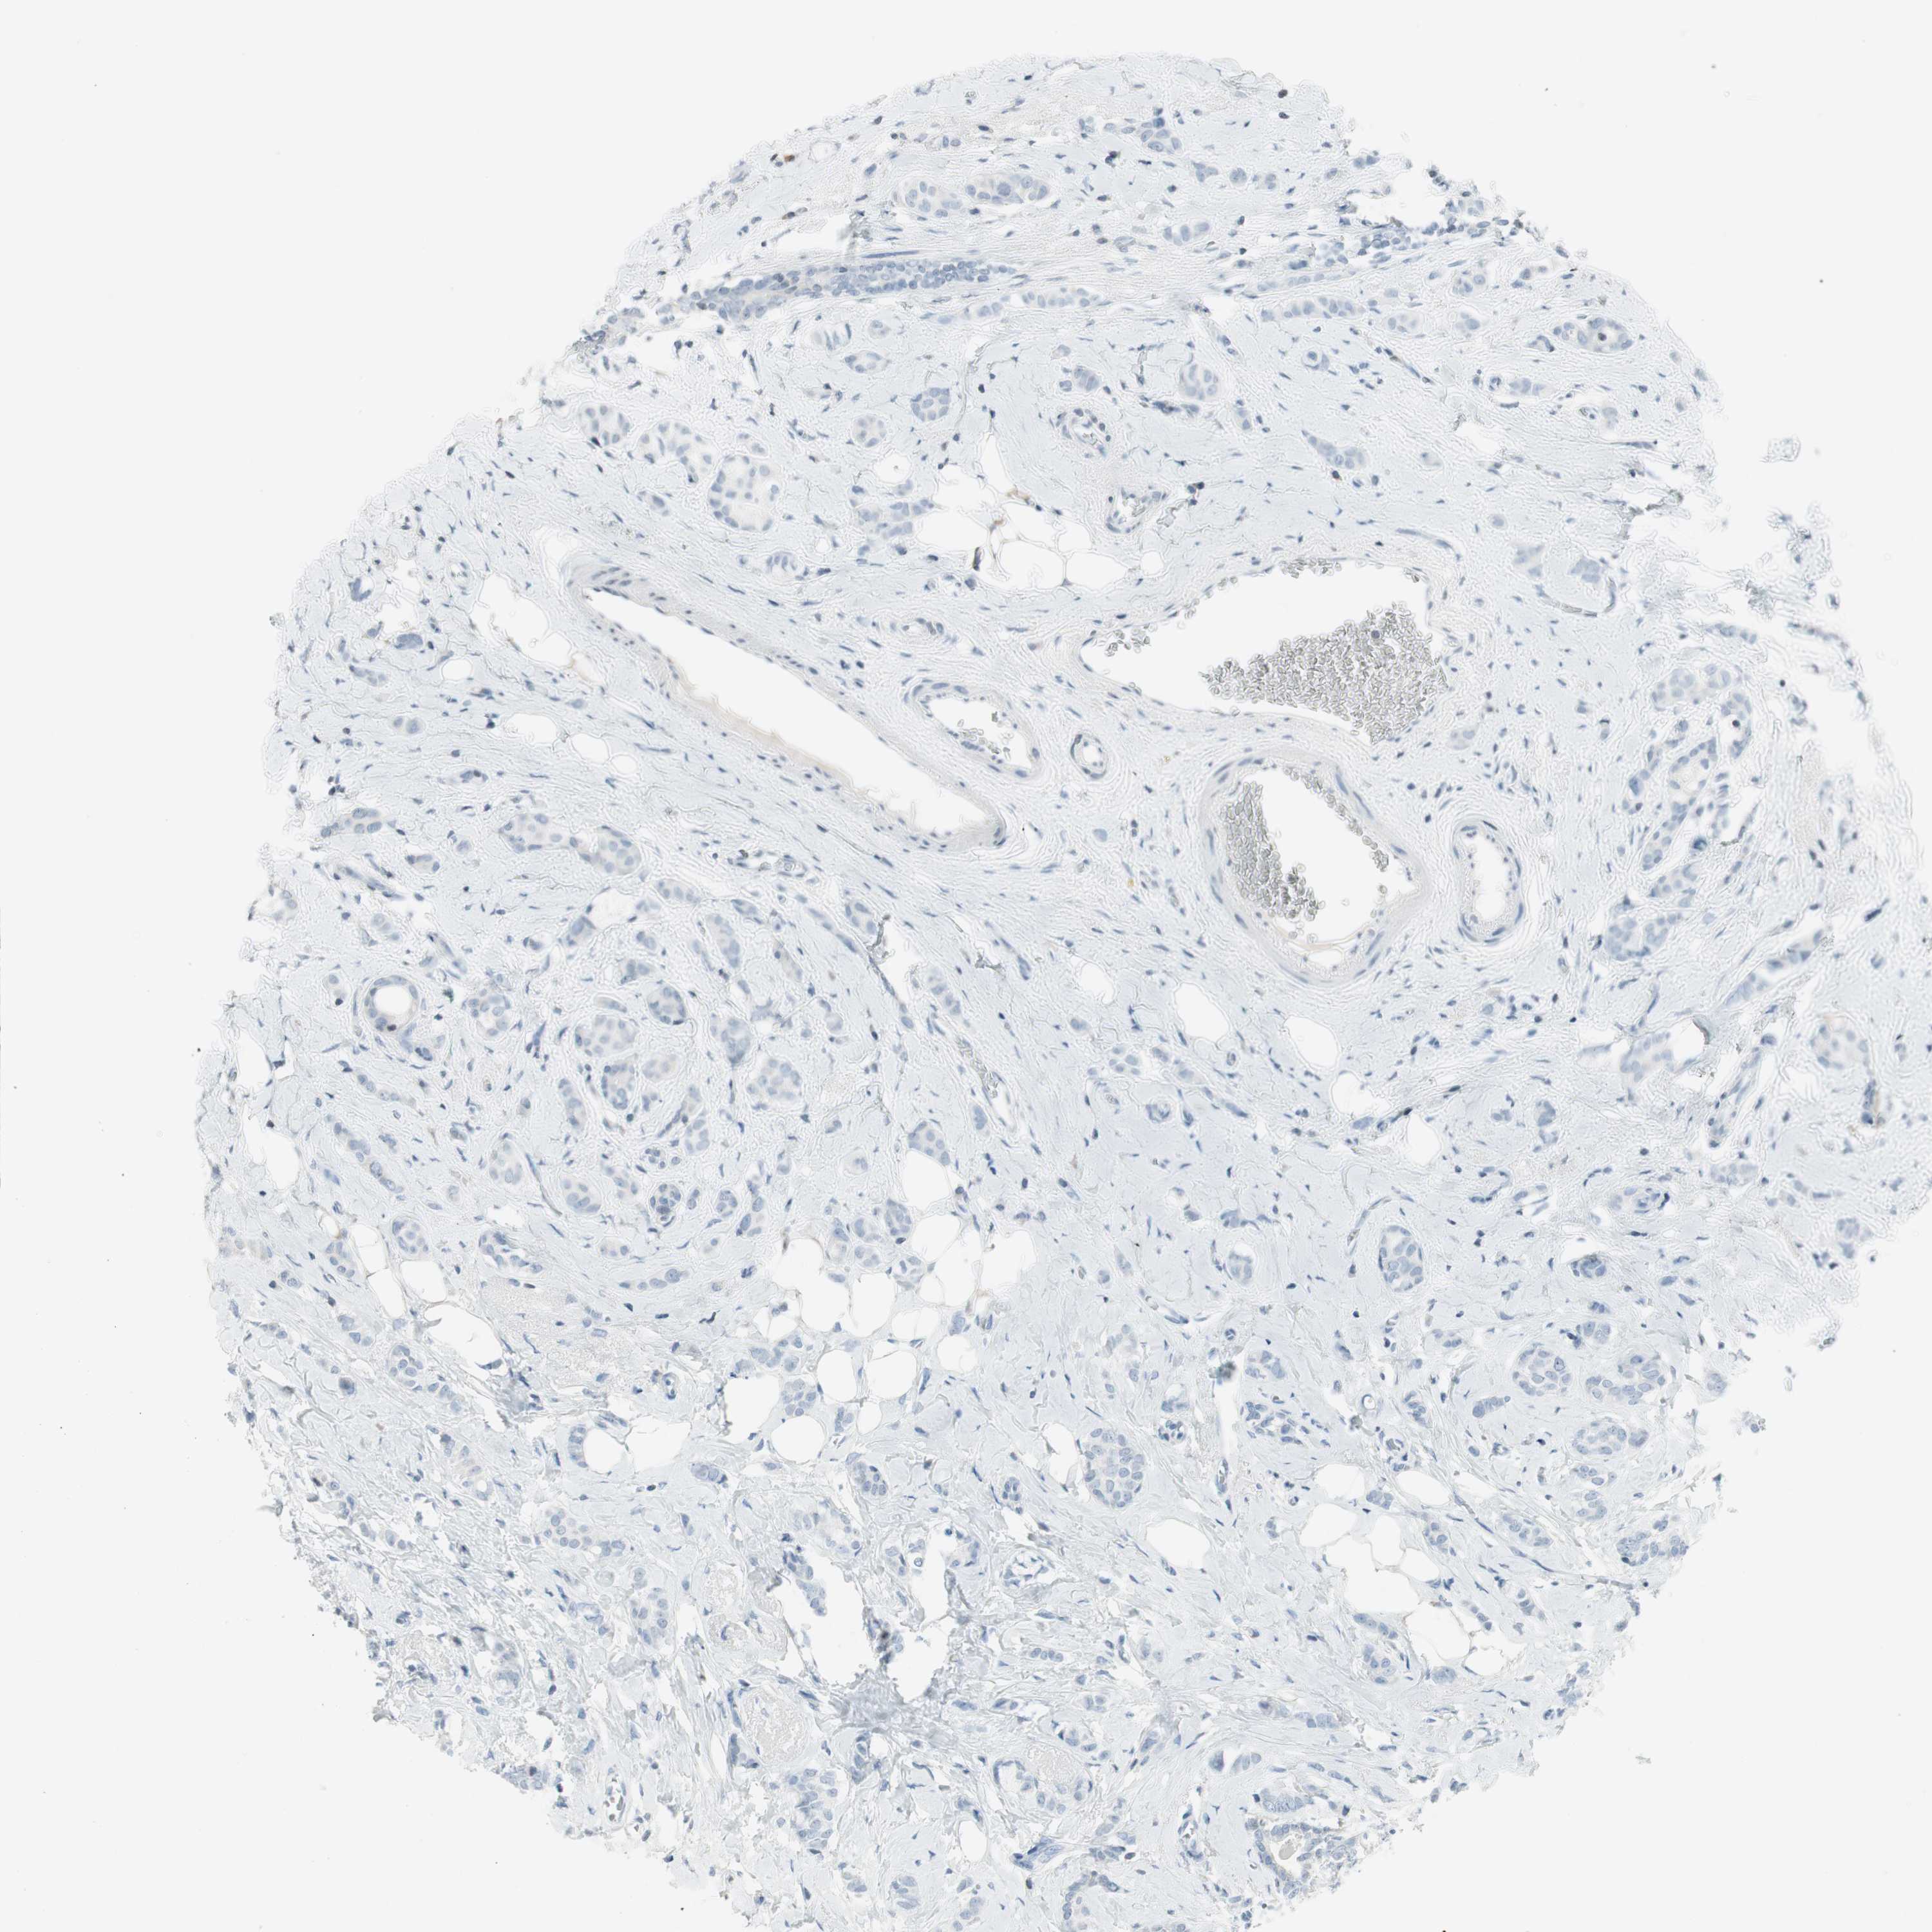

CANCER BREAST CANCER Show tissue menu

BRCA TCGA BRCA VALIDATION PROTEIN EXPRESSION

ANTIBODIES

AND

VALIDATION